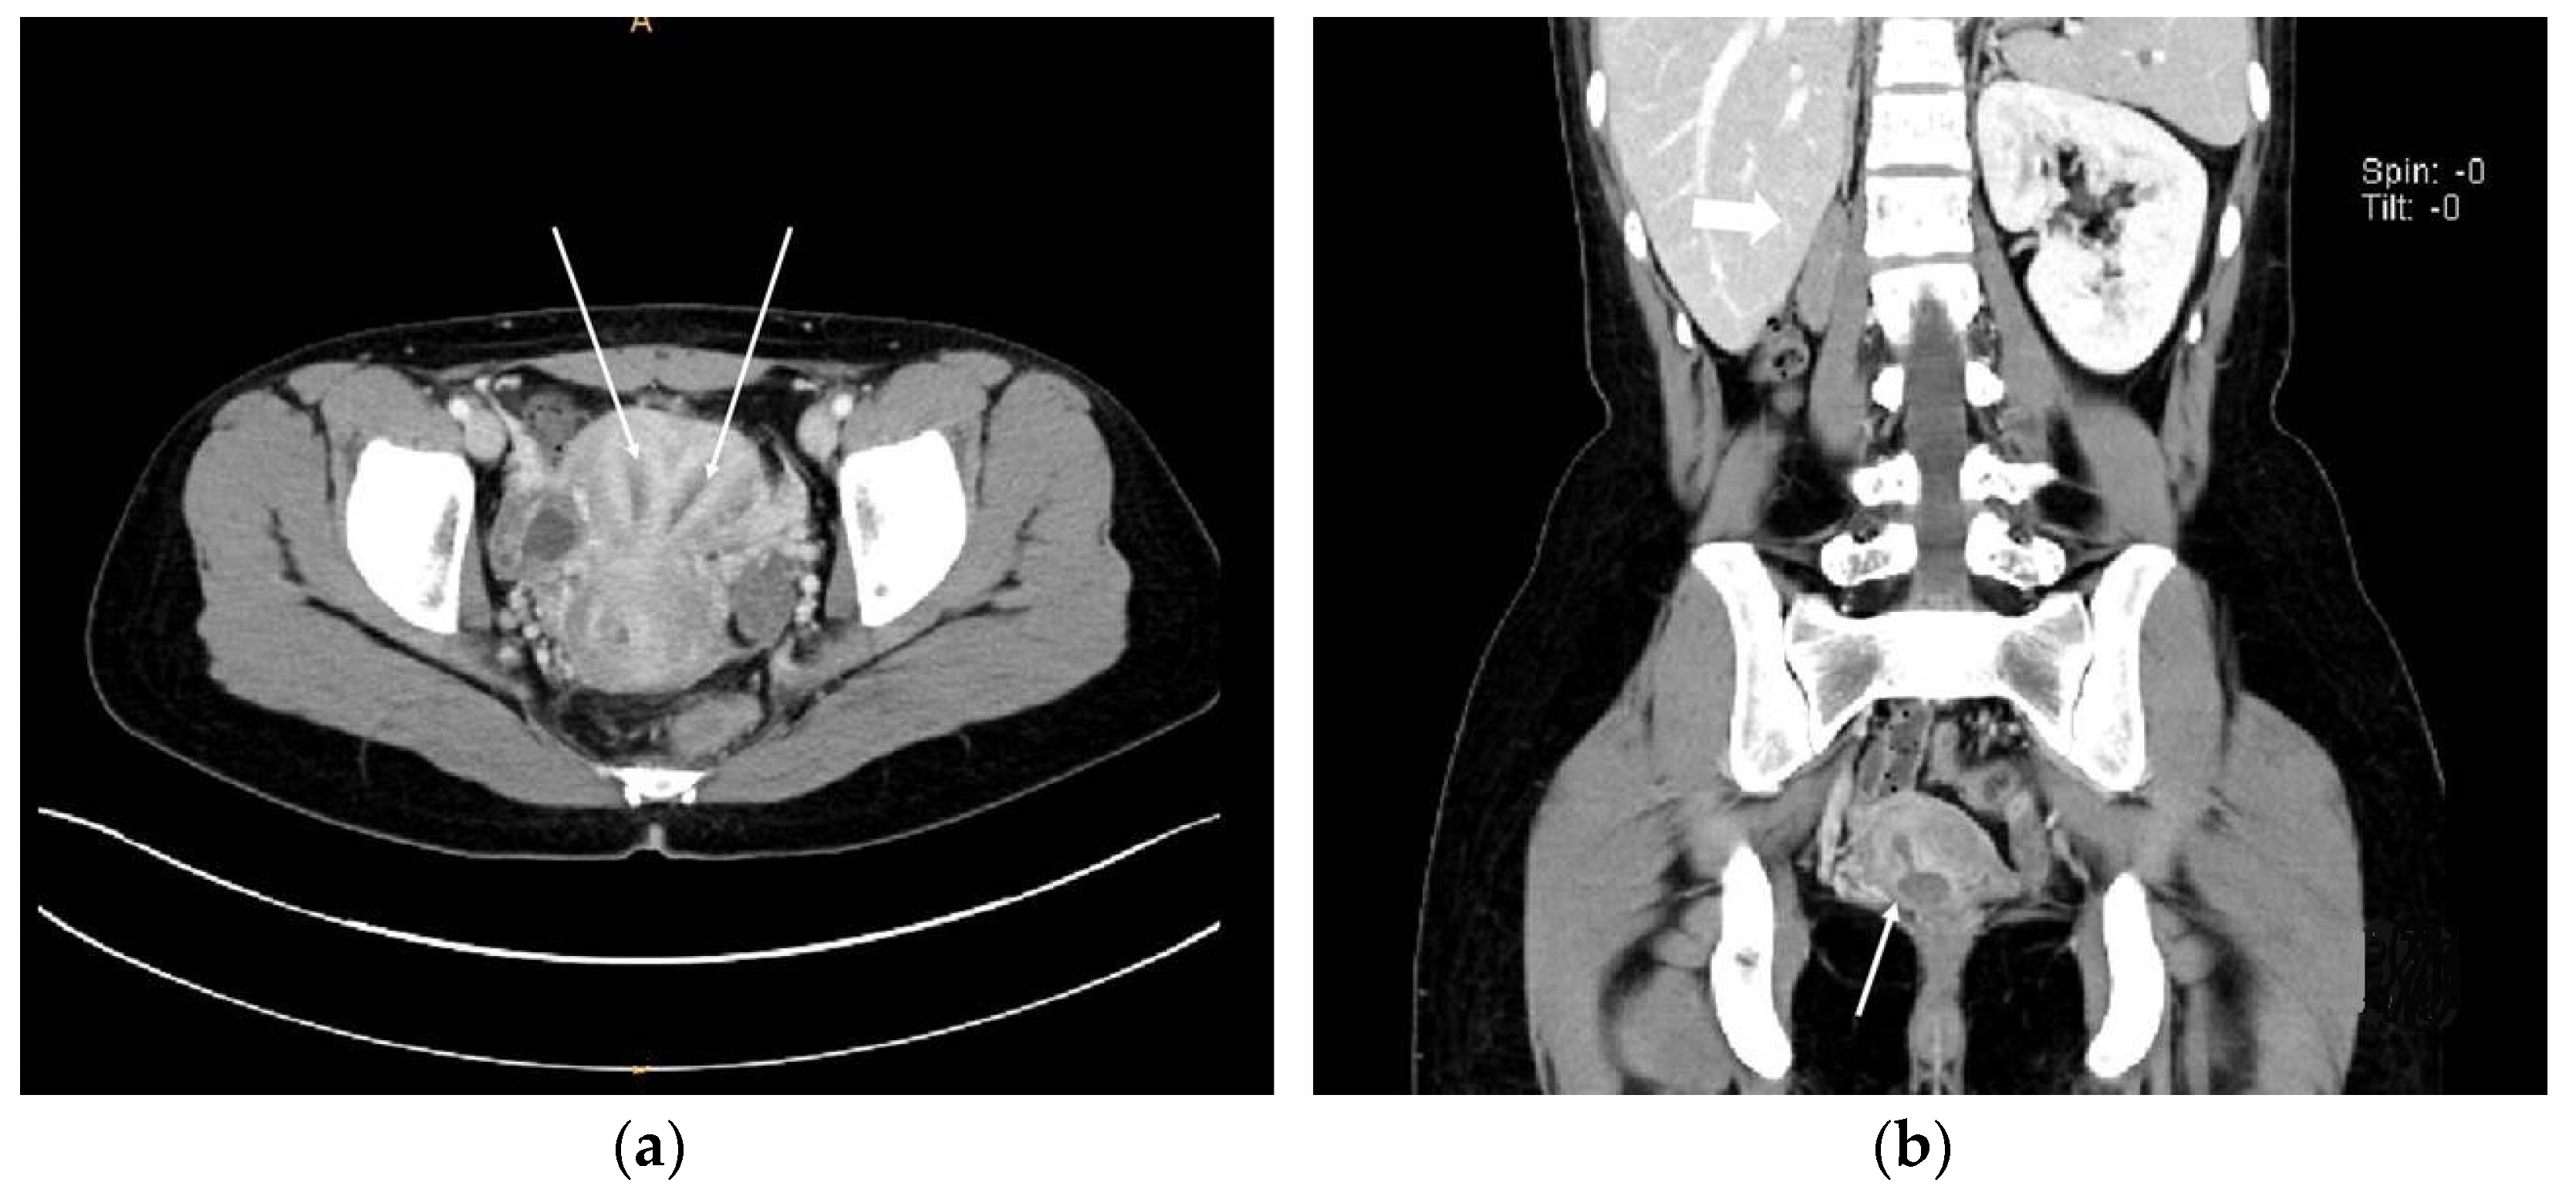

On the abdominopelvic CT image taken at the ER, we noticed she had HWW syndrome (right side hemi-vagina and right kidney agenesis) with acute pyelonephritis (APN) of the left kkidne (Figure 3a,b). After admission, transvaginal USG (Figure 4) and pelvic MRI (Figure 5a–c) were performed. We planned to perform the vaginal wall resection surgery on the next menstrual period as she needed antibiotics treatment for the APN, and the amount of hematocolpos was not so extensive that we could not clearly identify the bulging vaginal wall.

Figure 3. Abdominopelvic CT images. (a) Axial view showing the two uterine corpuses (indicated with white arrows); (b) Coronal view suggesting Herlyn-Werner-Wunderlich syndrome. White thick arrow; agenesis of right kidney. White thin arrow; hematocolpos of obstructed hemi-vagina connected with right endometrial cavity.